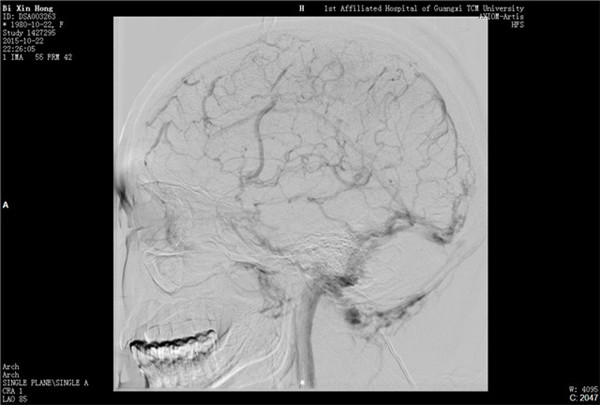

经与患者及家属充分沟通并获得同意后,外六科脑血管病介入治疗团队立即为患者行全脑血管造影,造影结果证实上矢状窦血栓形成,整个上矢状窦完全闭塞,若不采取措施病情很快就会恶化。再次征得家属同意后果断采取微导管介入手术治疗,手术在起病后当晚开始,由于患者血栓位置深在,需要经动、静脉双重途径置管,技术难度较大。术者选取Solitaire支架( 美国 公司)置入微导管远端,释放支架并在原位作短暂停留使支架与血栓充分接触并黏附,一起回撤支架与微导管取出血栓,手术一直持续到第二天凌晨。术后留置导管一条,用于每天以药物继续溶栓。术后患者即清醒,头痛明显缓解,无神经功能缺失。手术第二周时患者已经能够生活自理。2015年12月12日患者痊愈出院。

急诊脑血管造影:上矢状窦闭塞